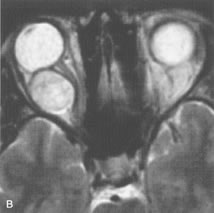

Lymphomas have MRI characteristics similar to those of inflammatory lesions in that they are hypointense to fat and isointense to muscle on T1-weighted images (Fig. 22). They may appear hyperintense to fat on T2-weighted images, perhaps owing to less fibrosis than that seen in orbital inflammatory pseudotumor, although this is not a consistent finding.31,50,66 Lymphoid tumors typically enhance moderately after contrast injection. Unfortunately, studies have shown that tumor density and homogeneity are similar between inflammatory and malignant orbital infiltrates, and MRI cannot differentiate these lesions.72,73

Fig. 22. A and B. T1- and (C) T2-weighted MR scans demonstrate a poorly defined multicompartmental mass enveloping the lateral rectus, superior rectus, and levator palpebrac superioris muscles. The lesion is isointense to brain on T1- and T2-weighted scans, as is typical for highly cellular neoplasms. D. Postcontrast fat-suppressed T1-weighted scan demonstrates intense enhancement of the infiltrating intraconal and extraconal tumor.